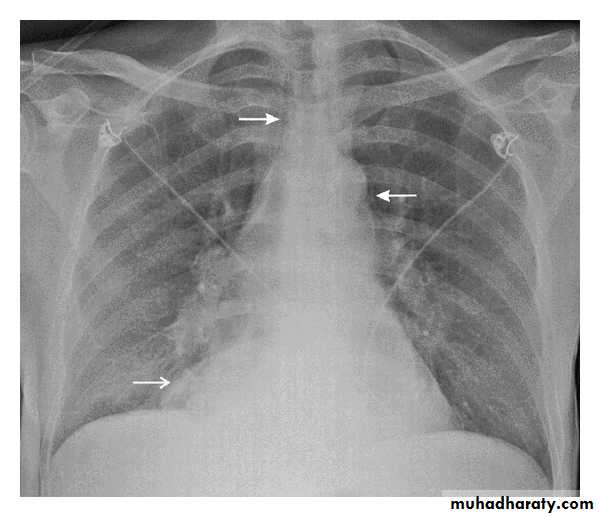

Perforation

Spontaneous perforation (boerhaave):Occur when a person vomit against closed glottis so the pressure increase rapidly and perforating the esophagus at its weakest point.

Clinical features: 1.chest pain

2. abdominal pain

3. dyspnea

Diagnosis:

• Chest x-rayFigure5: CXR showing air in the medistinum

• 2. Water soluble contrast• 3. CT scan

Figure6: contrast material free in the abdomen